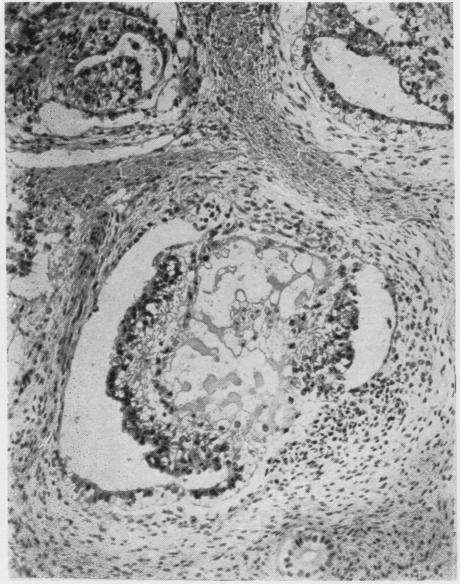

Developmental stages of embryo-like bodies in teratoma testis.